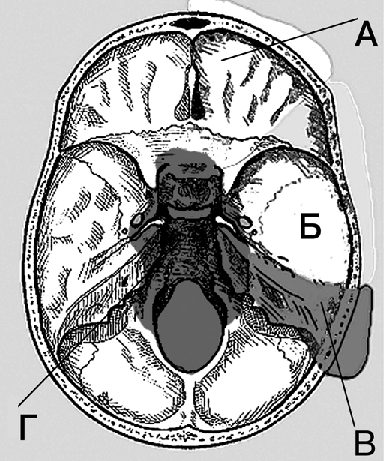

У больных с III стадией опухолевого процесса хирургическое вмешательство, заключающееся в максимально возможном удалении опухоли, приводит к образованию обширных дефектов черепа и мягких тканей, которые необходимо закрывать с применением различных методов пластики. Области хирургической доступности (возможности радикального удаления опухоли основания черепа) схематично представлены на рисунке 1. Медиальные отделы основания черепа (зона Г) не могут быть включены в блок, расположенные там опухоли относятся к Т4 стадии.

Рисунок 1. Зоны локализации опухолей, доступные для радикального хирургического лечения (блок-резекции):